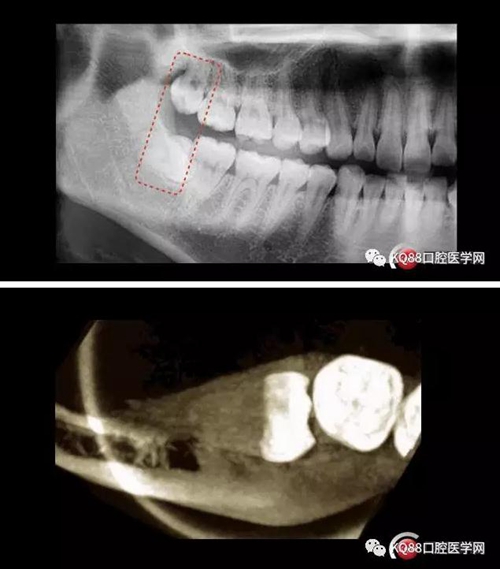

智齒拔除

此文關(guān)鍵字:智齒拔除